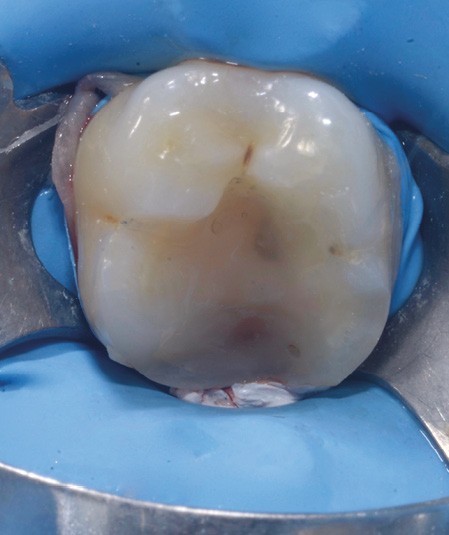

Lors de la préparation d’une cavité pour inlay/onlay, il est fréquent d’être confronté, en fin de nettoyage, à la présence d’une ou plusieurs parois résiduelles dont la résistance mécanique paraît douteuse du fait de leur localisation ou de leur épaisseur. Les parois épaisses (+ de 2 mm) peuvent généralement être conservées (cas clinique 1) et les parois fines (- de 1 mm) doivent généralement être recouvertes. Un inlay (en composite ou en céramique) est alors réalisé. Il doit avoir lui même, au final, une épaisseur globale minimale de 2 mm pour assurer sa résistance mécanique intrinsèque à la mastication. Si un recouvrement cuspidien est indiqué, la réduction occlusale doit donc se faire sur 2 mm de hauteur au minimum [1, 2].

Mais qu’en est-il des parois résiduelles d’épaisseur intermédiaire (entre 1 et 2 mm) (cas clinique 2) ?